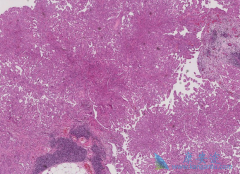

滤泡淋巴瘤(FL)通过利妥昔单抗( Rituximab )治疗得到改善。在瑞典,2003-2007年间,不同地区逐渐引入一线利妥昔单抗疗法。2007年首次发布的滤泡淋巴瘤国家指南建议利妥昔单抗作为一线疗法。   根据基于人群的瑞典淋巴瘤注册,2000-2010年,2641名患 ...